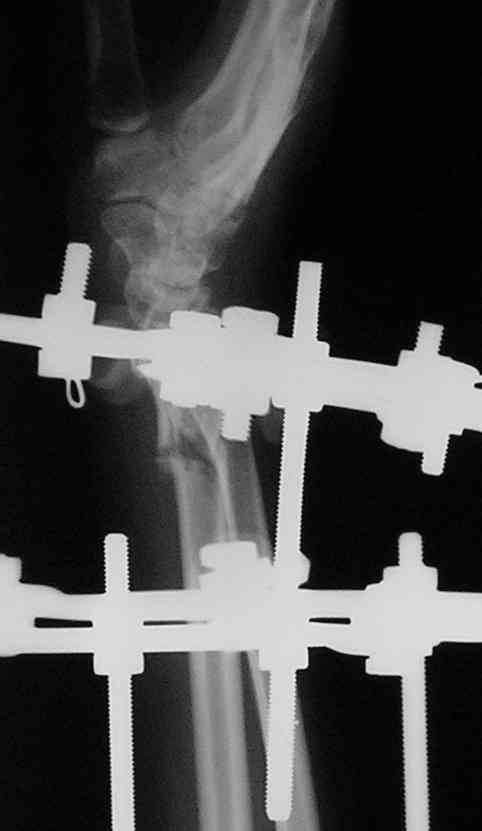

Спице-стержневой аппарат с компактотомией лучевой кости, костная пластика локтевой с удалением пластины. Не комфортно, но больше шансов на благоприятный исход. Заканчиваю лечение с похожей деформацией лучевой кости.

У больного/ой кроме перелома лучевой кости и шиловидного отростка локтевой, разрыв дистального радиоульнарного сочленения, перелом ладьевидной кости и ладьевидно-полулунная диссоциация.

Если позволите свое мнение, не стал бы лечить аппаратом эту травму, перелом луча не консолидировался: открытая репозиция+ костная пластика+ пластина, синтез ладьевидной кости, по возможности шов ладьевидно полулунной связки,

если восстановить связку не представляется возможным, фиксация 2 спицами.